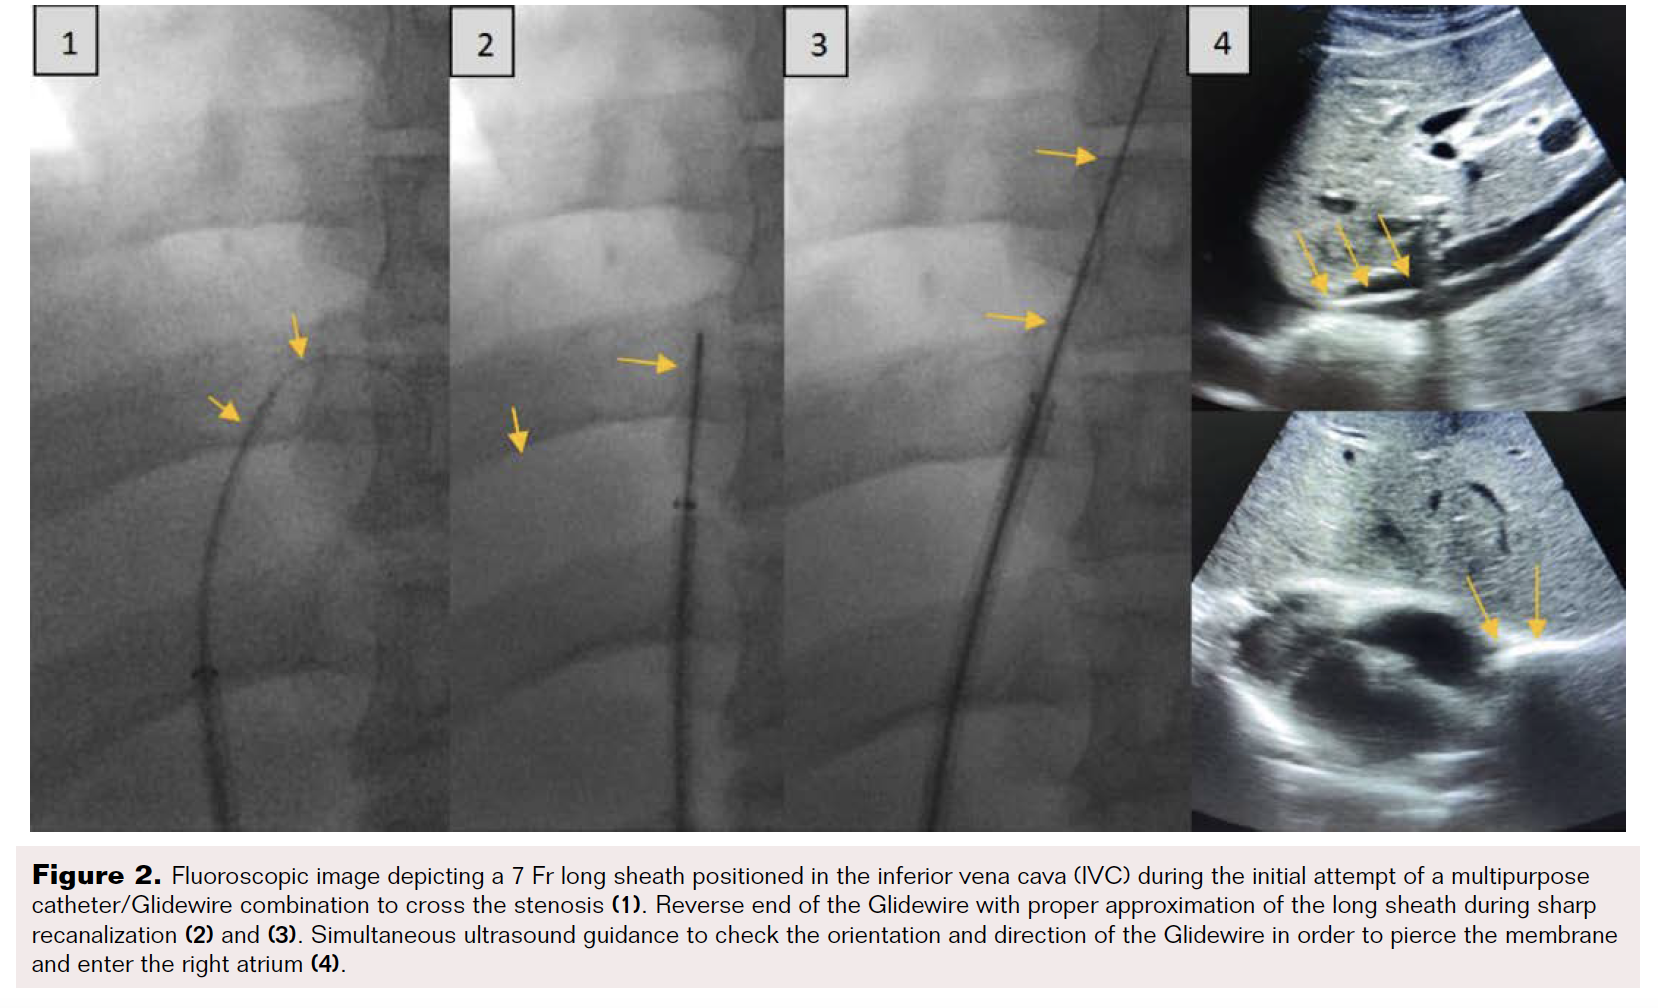

The procedure was performed in the angiography room under local anesthesia. The right common femoral vein was accessed under US guidance, and a 7 Fr sheath was placed. A 5 Fr pigtail catheter was placed in the infrahepatic IVC. Under fluoroscopy and transabdominal US guidance, a few attempts were made with a 5 Fr multipurpose catheter and stiff Glidewire (Terumo). Using real-time US guidance, the short-segment occluded IVC was traversed by the backend of a stiff Glidewire. After confirming the wire was well within the right atrium on US, the catheter was advanced under fluoroscopy a short distance into the right atrium. The Glidewire end was reversed, and the catheter was advanced into the right atrium (Figure 2).

The Glidewire was exchanged for a 0.035" Amplatz exchange-length wire. Serial balloon angioplasty was performed using 8 mm, 12 mm, and 14 mm diameter balloons. Recanalization of the suprahepatic IVC occlusion was observed on US (Figure 3).